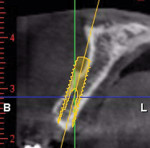

A healthy 27-year-old female oral surgery resident was referred to the author’s private office for implant replacement of missing tooth No. 7. A CBCT revealed inadequate ridge width (3 mm to 3.4 mm) for the placement of a 3.3-mm diameter implant in ideal prosthetic position (Figure 4). Horizontal augmentation was proposed and consent signed. The patient began taking amoxicillin (1.5 g/day) one day prior to the surgical appointment. She rinsed with 0.12% chlorhexidine gluconate for 1 minute just before the procedure. Four 9-ml tubes (Vacuette® blood collection tubes, Intra-Lock International, www.intra-lock.com) of whole blood were collected with a butterfly needle (Vacuette® Butterfly Blood Collection Set, Intra-Lock International). The blood was immediately spun in a dedicated L-PRF centrifuge (IntraSpin®, Intra-Lock International) at 2,700 rpm for 12 minutes. During the blood spin, local anesthesia was administered (xylocaine 2% with epinephrine 1/100,000).

Six months later, a new CBCT revealed substantial lateral augmentation to the full extent of pin projection (Figure 12). Ridge width had been increased more than 4 mm with sufficient bone volume for the placement of a 3.5-mm x 13-mm implant (Nobel Biocare, www.nobelbiocare.com) (Figure 13). A small volume of mineralized freeze-dried cortical bone was added to eliminate the surgically created apical undercut. Additional L-PRF membranes were placed along with a 3-mm healing cap (Figure 14), and the implant submerged to increase marginal soft-tissue volume.